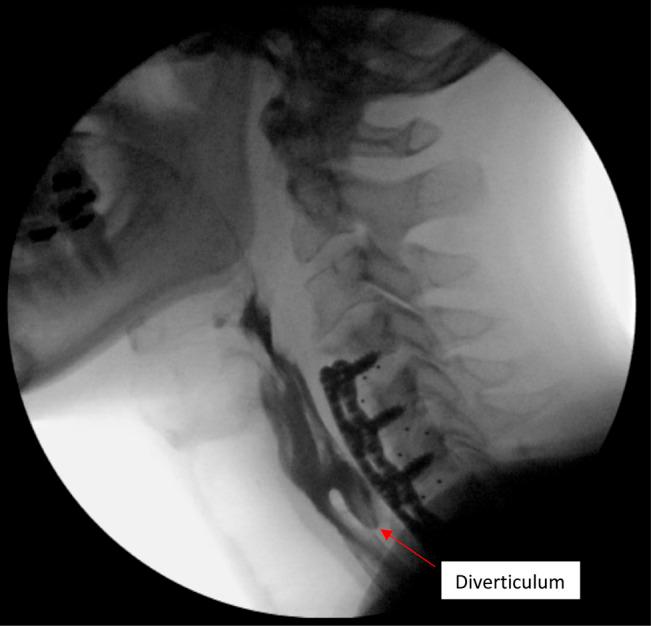

Delayed Esophageal Perforation Diagnosed 12 Years After Anterior Cervical Diskectomy and Fusion: A Case Report and Review of Current Literature.

Esophageal perforation associated with anterior cervical diskectomy and fusion (ACDF) is a rare but serious complication. ACDF-related esophageal perforations can be acute or delayed. Delayed perforations more than 10 years after ACDF are exceedingly rare. Here, a delayed esophageal perforation discovered 12 years after a three-level ACDF is presented. This case highlights two main points. First, all diverticula after an ACDF warrant close clinical monitoring. Second, routine follow-up should be performed for patients with screw pullout to assist in early diagnosis of delayed esophageal perforation.